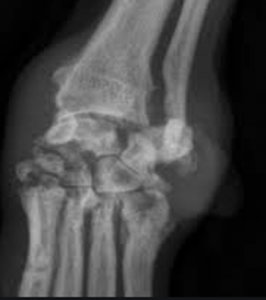

The most commonly affected joints are carpus, tarsus, stifle, and elbow. However, any joint can be affected. Erosive IMPA causes bone destruction and in advanced cases, joint collapse of digits, carpi, and tarsi are not uncommon. This is due to subsequent damage to supporting soft tissues. Non-erosive IMPA presents with effusion or no effusion, joint pain or no pain, and no joint instability or bone destruction.

Diagnosis of IMPA begins with a level of suspicion based on the above clinical signs. Certainly, joint collapse as is seen with erosive forms is telling as are supportive radiographs revealing bone lysis (so-called “punched out” lesions”). In order to confirm and categorize non-erosive IMPA, a complete work up guided by clinical presentation including the steps listed in box 2 is ideal.

Radiographs can reveal erosive lesions sometimes called “punched out” regions as well as significant joint collapse in advanced cases.